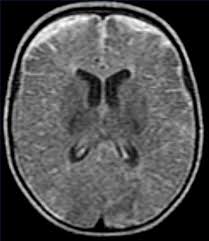

- Imagen por resonancia magnética: la administración de gadolinio facilita el diagnóstico al reforzar el anillo del empiema y diferenciar el empiema respecto del parénquima cerebral subyacente.

- La resonancia magnética craneal es también muy útil para identificar sinusitis, otras infecciones focales del sistema nervioso central, infartos venosos corticales, edema cerebral y cerebritis.

- La tomografía puede revelar una lesión hipodensa semilunar sobre uno o ambos hemisferios o en la cisura interhemisférica, efecto de masa en expansión, desplazamiento de estructuras desde la línea media, compresión ventricular y borramientos de surcos